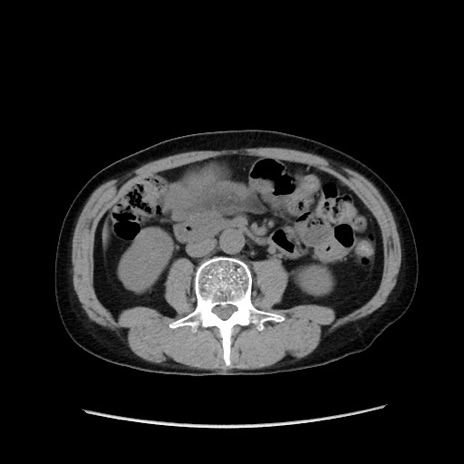

症例37(横断像)

【症例】40歳代 男性

【主訴】腹痛

【現病歴】4時間ほど前に電車に乗車中に臍部上より腹痛出現。徐々に増悪し起立困難となり、救急外来受診。生ものは数日食べていない。今朝お雑煮を食べた。

【身体所見】BT 36.8℃、BP 117/84mmHg、HR 91/min、SpO2 97%、苦悶様、腹部:臍上部広範囲圧痛あり、反跳痛±

【データ】WBC 8100、CRP 0.03